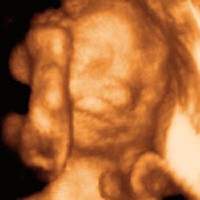

Photo studio in utero

During an ultrasound procedure, sound waves from a transducer placed on the mother’s abdomen are emitted and reflected off the fetus to create an image on the monitor screen. This technology has been in use for about the last 50 years and has a good safety record. Harmful effects in human cells have not been shown by the bulk of published scientific studies.